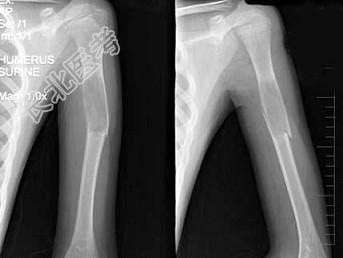

- 单项选择题男,13岁, 因轻微外伤后感左肱骨上部疼痛,软组织肿胀, 摄片见左肱骨上段局限性骨质沿髓腔膨胀性破坏,骨皮质变薄, 部分骨皮质不连续,最可能的诊断是 ( )

B、左肱骨骨囊肿伴病理性骨折